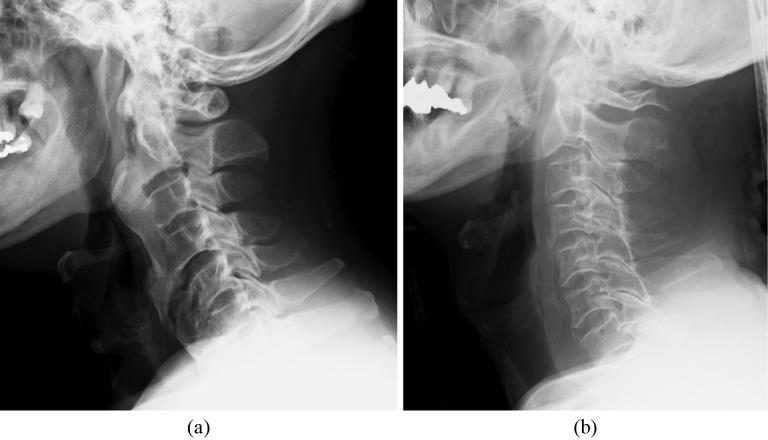

Abstract Image